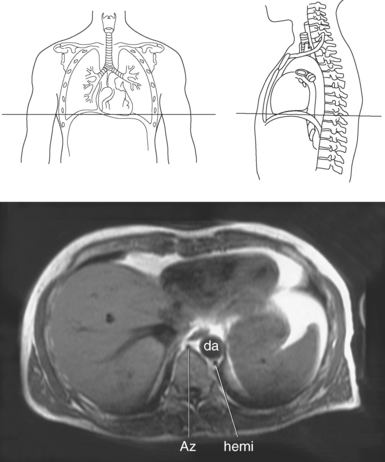

The azygos venous system, which provides collateral circulation between the inferior and superior venae cavae, can be divided into the azygos and hemiazygos veins (Figure 6.103). Together, they drain blood from most of the posterior thoracic wall and from the bronchi, pericardium, and esophagus. The azygos vein ascends along the right side of the vertebral column, whereas the hemiazygos vein ascends along the left side. The hemiazygos vein crosses to the right behind the aorta to join the azygos vein at approximately T7-T9. The azygos vein then arches over the hilum of the right lung to empty into the posterior superior vena cava (Figures 6.104 and 6.105).

Muscles associated with respiration are the intercostal, serratus posterior superior, serratus posterior inferior, and the diaphragm (Table 6.3). The spaces between the ribs, or the intercostal spaces, are filled with three layers of intercostal muscles (external, internal, and innermost layer) (Figures 6.106 through 6.108). These muscles act together to elevate the ribs and expand the thoracic cavity, as well as keep the intercostal spaces somewhat rigid. The serratus posterior superior muscle spans from C7-T2 to ribs 2 to 5 and acts to assist forced inspiration, whereas the serratus posterior inferior muscle spans from T11-L2 to ribs 9 to 12 and acts to assist forced expiration (Figures 6.109 through 6.110). The diaphragm is a large dome-shaped muscle that spans the entire thoracic outlet and separates the thoracic cavity from the abdominal cavity (Figure 6.111). It is the chief muscle of inspiration because it enlarges the thoracic cavity vertically as the domes move inferiorly and flatten. The muscle fibers of the diaphragm converge to be inserted into a central tendon, which is situated near the center of the diaphragm immediately below the pericardium, with which it is partially blended. The diaphragm is attached to the lumbar spine via two tendinous structures termed crura (Figures 6.111 through 6.113). The right crus arises from the anterior surfaces of L1-L3, whereas the left crus arises from the corresponding parts of L1-L2 only. The left and right crura join together across the ventral aspect of the abdominal aorta to form the medial arcuate ligament. Three major openings, or hiatuses, of the diaphragm allow for the passage of vessels and organs from the thorax to the abdomen. The aortic hiatus allows for the passage of the descending aorta, azygos vein, and thoracic duct. The caval hiatus allows for the passage of the inferior vena cava and the right phrenic nerve. The esophageal hiatus allows for the passage of the esophagus and the vagus nerve.